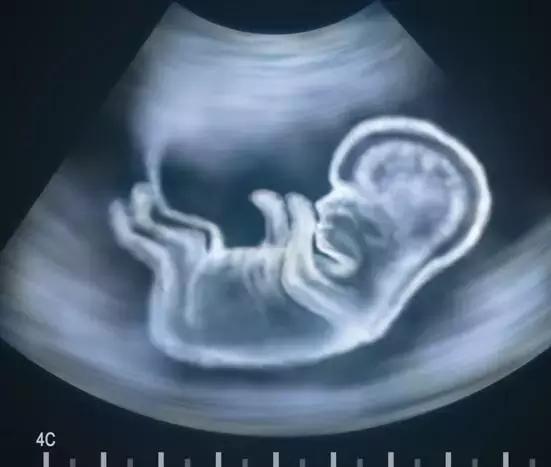

胎膜早破是指在子宫收缩开始之前的胎膜就破了,在妊娠37周之前发生的胎膜早破被称为早产胎膜早破(PPROM)。

而妊娠37周后发生的PROM称为足月胎膜早破,以上妈妈都是临近分娩出现的破水,都是足月胎膜早破。

胎膜由内羊膜和外绒毛膜组成。在足月,羊膜是坚韧但柔韧的膜,这种最内侧的无血管胎膜与羊水相邻,在人类怀孕中起着非常重要的作用。羊膜几乎提供了胎膜的所有拉伸强度。

而胎膜一旦破裂,就说明与之相邻的羊水也就没有了保护伞,与此同时,羊水也会开始泄露,如果没有及时发现,可能会带来严重并发症。

如果胎膜早破没有被及时发现,羊水的泄露会导致低羊水水平,还会增加感染的风险。

我们都知道羊水是婴儿生命支持系统的一部分。它可以保护宝宝,帮助宝宝肌肉,四肢,肺部和消化系统的发育。随着婴儿的成长,他或她将在羊水的帮助下在子宫内移动和翻滚。